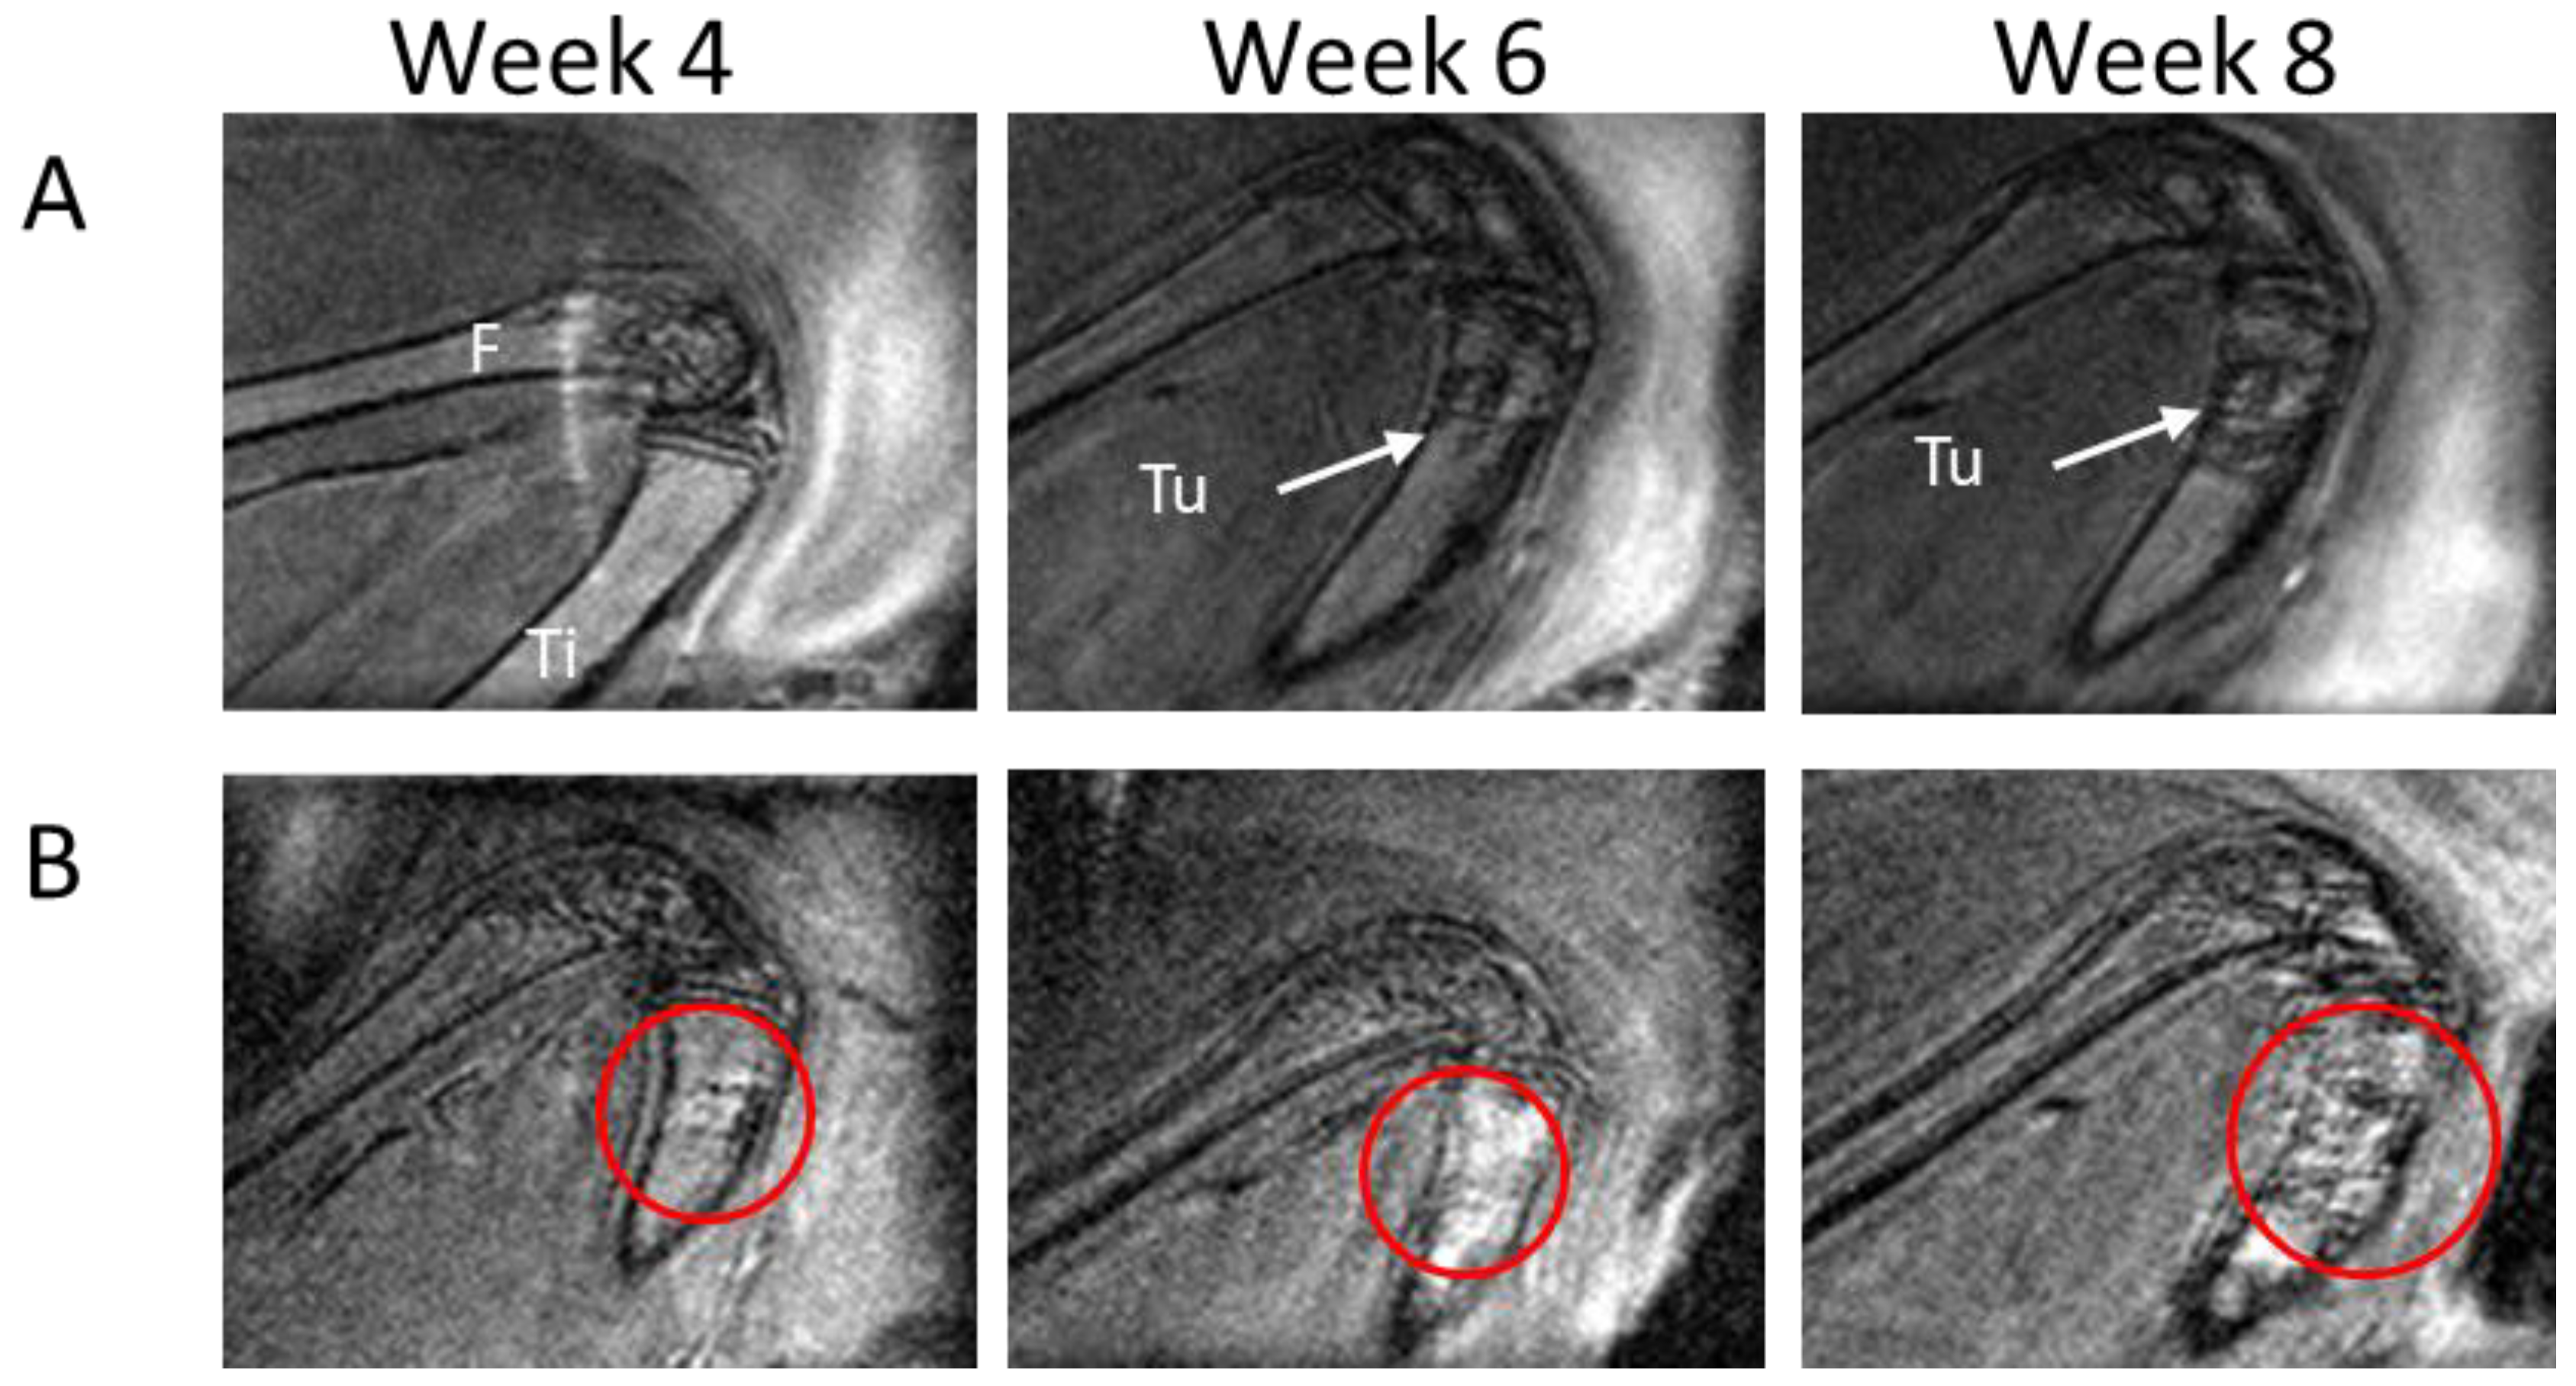

3.3. MRI Performance in Assessing Tumor Growth